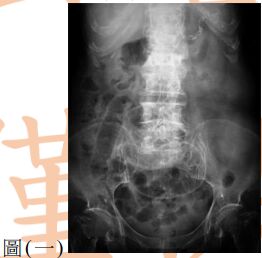

13. 80歲女性為長期糖尿病、高血壓及中風不良於行之病人,因急性腹痛來急診就醫,其平躺之腹部X光如圖(一),另一張左側躺之腹部X光檢查如圖(二),下列敘述何者正確?(A) 推測有腹腔積水,可能為腹腔腫瘤導致 (B) 推測有腹部脹氣,可能為腸阻塞導致 (C) 推測有腹腔積氣,可能為腹腔內中空臟器破裂導致 (D) 為正常腹部影像,只須持續追蹤